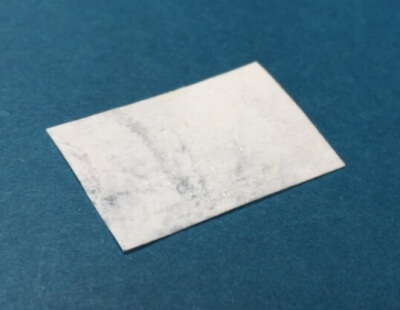

Костно-пластические материалы для имплантологии: подробный обзор

Продукт, которого нет ни у кого!!!